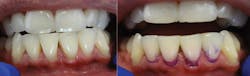

Figure 2 is an example of what appears to be a healthy mouth, and the result when the papillary bleeding test is administered.

When patients see the bleeding they routinely ask, “How do I stop the bleeding?” This question opens the door for you to end “bloody prophies.” The moderate pressure that cleans and disturbs the biofilm and granulation tissue is responsible for the bleeding. Be sure to explain to patients that healthy tissue does not bleed or hurt when touched with tools such as the Soft-Pick. Tissues shrink and go from healthy-looking beer belly gums to six-pack abs in three days. Therefore, the PBS is the “truth serum” for infection and shows whether your patients are cleaning between their teeth. This is the first and most important change to make in their daily routine.